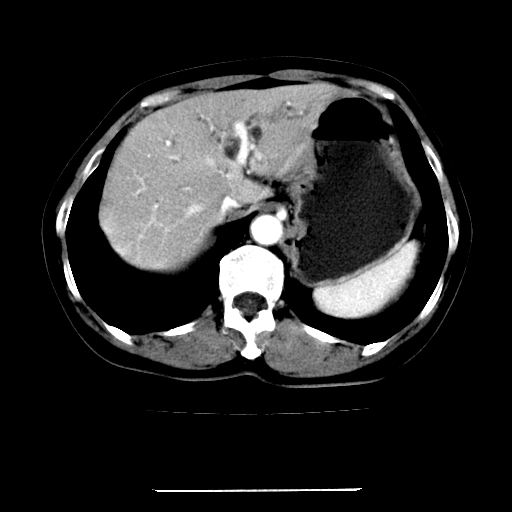

标题: CT22301:女,67岁,上腹部疼痛一周伴皮肤黄染,无发热。 [打印本页]

女,67岁,上腹部疼痛一周伴皮肤黄染,无发热。

左叶肝内胆管结石,并远端肝内胆管扩张。

考虑:肝内胆管结石继发肝内胆管扩张,右肾旋转不良。

肝内外胆管结石并肝内胆管扩张。

建议薄层观察,除外肝门部胆管细胞癌

考虑肝胆管癌;胰头占位?【形态失常,体积增大】

1、肝门高密度影下层面和胰头层面可见轻度胆管扩张,而静脉和延迟期均未见扫描完胰头,不能完全排除胰头占位。2、肝门部高密度影,考虑钙化或结石。

考虑肝门胆管癌伴门脉左支受侵包埋,建议mrcp进一步检查。